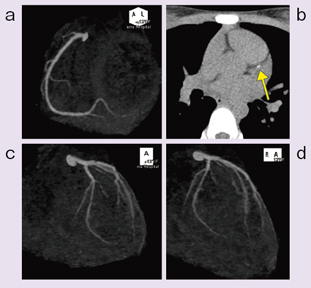

Amazon.com: CT冠動脈造影実践学: 9784498013568: unknown